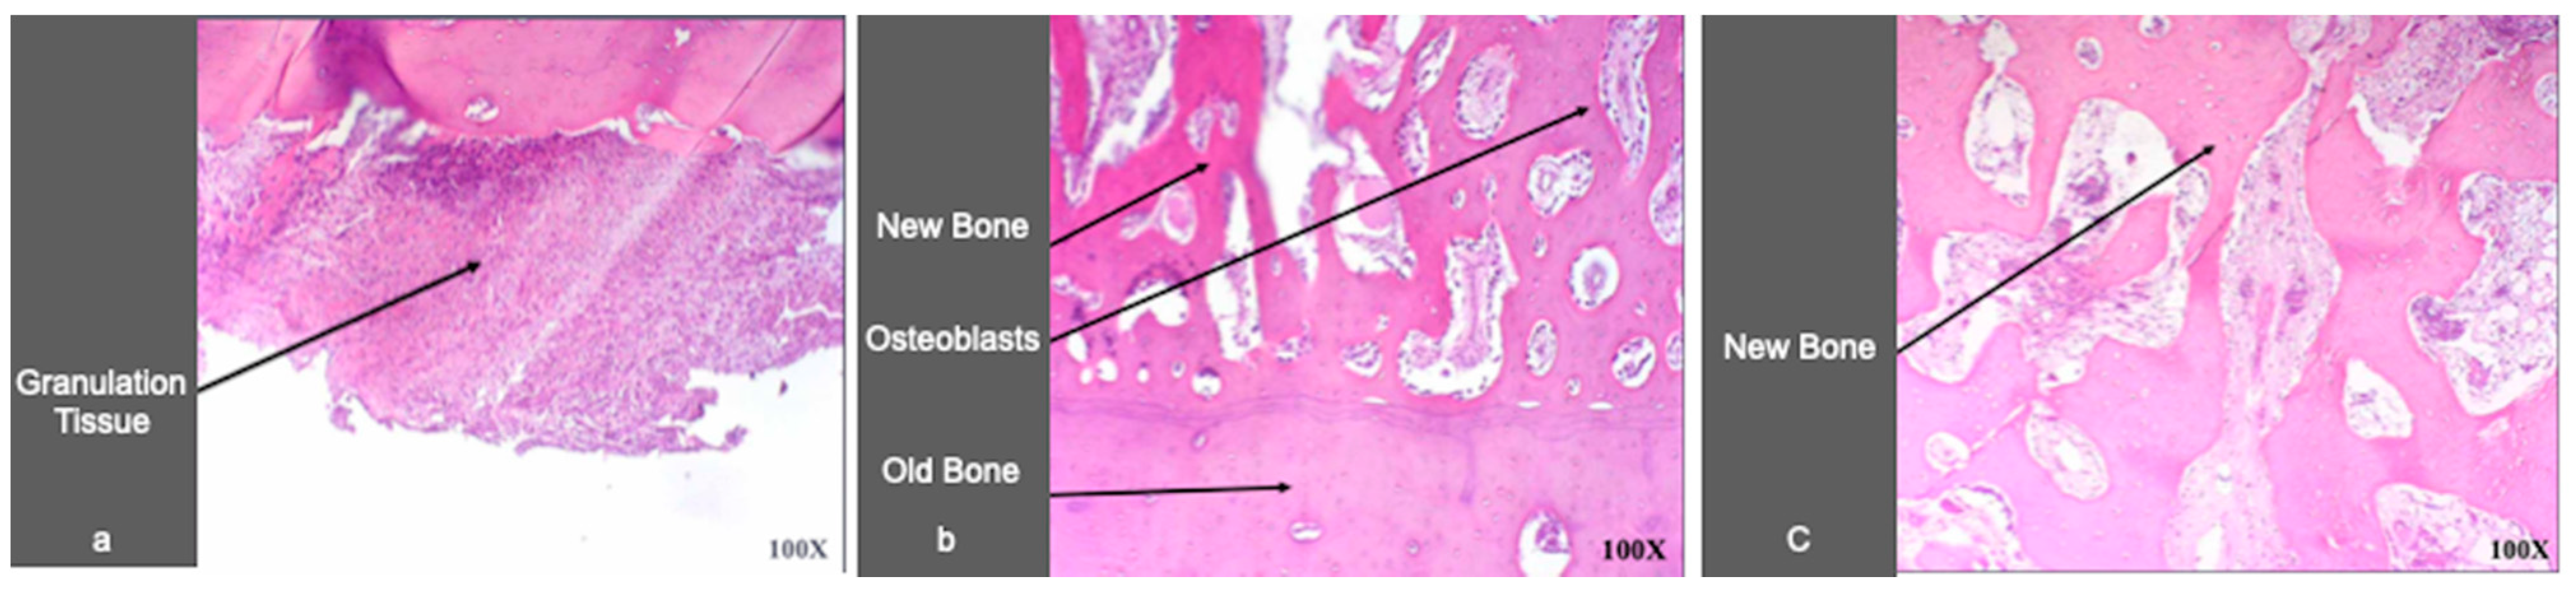

2.3. Histological Analysis

3.1. Histological Analysis

4.3. Histological Analysis